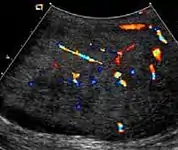

Fig. 10. Epidermoid cyst. Onion peel appearances of the tumor together with absence of vascular flow are typical findings of epidermoid cyst.

Epidermoid cysts, also known as keratocysts, are benign epithelial tumors which usually occur in the second to fourth decades and accounts for only 1–2% of all intratesticular tumors. As these tumors have a benign biological behavior and with no malignant potential, preoperative recognition of this tumor is important as this will lead to testicle preserving surgery (enucleation) rather than unnecessary orchiectomy. Clinically, epidermoid cyst cannot be differentiated from other testicular tumors, typically presenting as a non-tender, palpable, solitary intratesticular mass. Tumor markers such as serum beta-human chorionic gonadotropin and alpha-feto protein are negative. The ultrasound patterns of epidermoid cysts are variable and include:

However, these patterns, except the latter one, may be considered as non-specific as heterogeneous echotexture and shadowing calcification can also be detected in malignant testicular tumors. The onion peel pattern of epidermoid cyst [Fig. 10] correlates well with the pathologic finding of multiple layers of keratin debris produced by the lining of the epidermoid cyst. This sonographic appearance should be considered characteristic of an epidermoid cyst and corresponds to the natural evolution of the cyst. Absence of vascular flow is another important feature that is helpful in differentiation of epidermoid cyst from other solid intratesticular lesions.